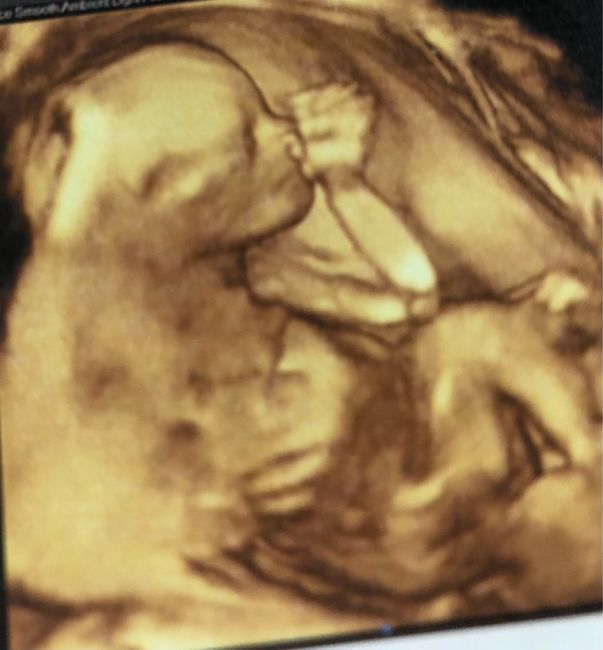

Ciao mamme e future mamme! Questa Pasqua ci porterà un altro Pulcino. Sono già mamma di Jacopo di un anno e l’anno prossimo saremo in 4. Chi altra mamma di aprile? ❤️